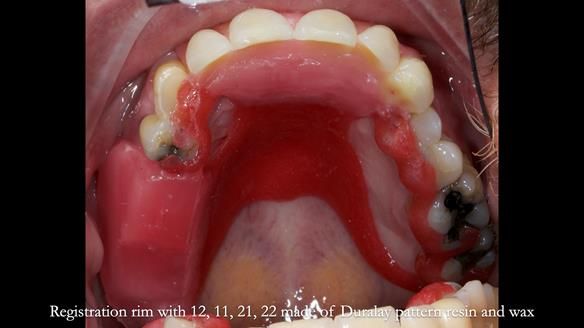

Keith’s case was one of the most challenging and rewarding cases I’ve treated this year. This 64 year old man presented with ill-fitting acrylic partial dentures that lacked stability, retention, and aesthetics. They constantly broke. He had lost the upper front teeth in a road traffic accident in his early 20s. The unopposed teeth had erupted, taking up space. After careful planning, we made a durable, metal-based upper partial denture/splint to address his dental concerns. He loved the outcome.

1. Denture design: A custom cobalt-chromium framework was Scandinavian-designed to maximise stability, protect the remaining teeth, and allow for future additions if needed.

3. Definitive alginate impression in custom tray: Used to ensure a well-fitting RPD.